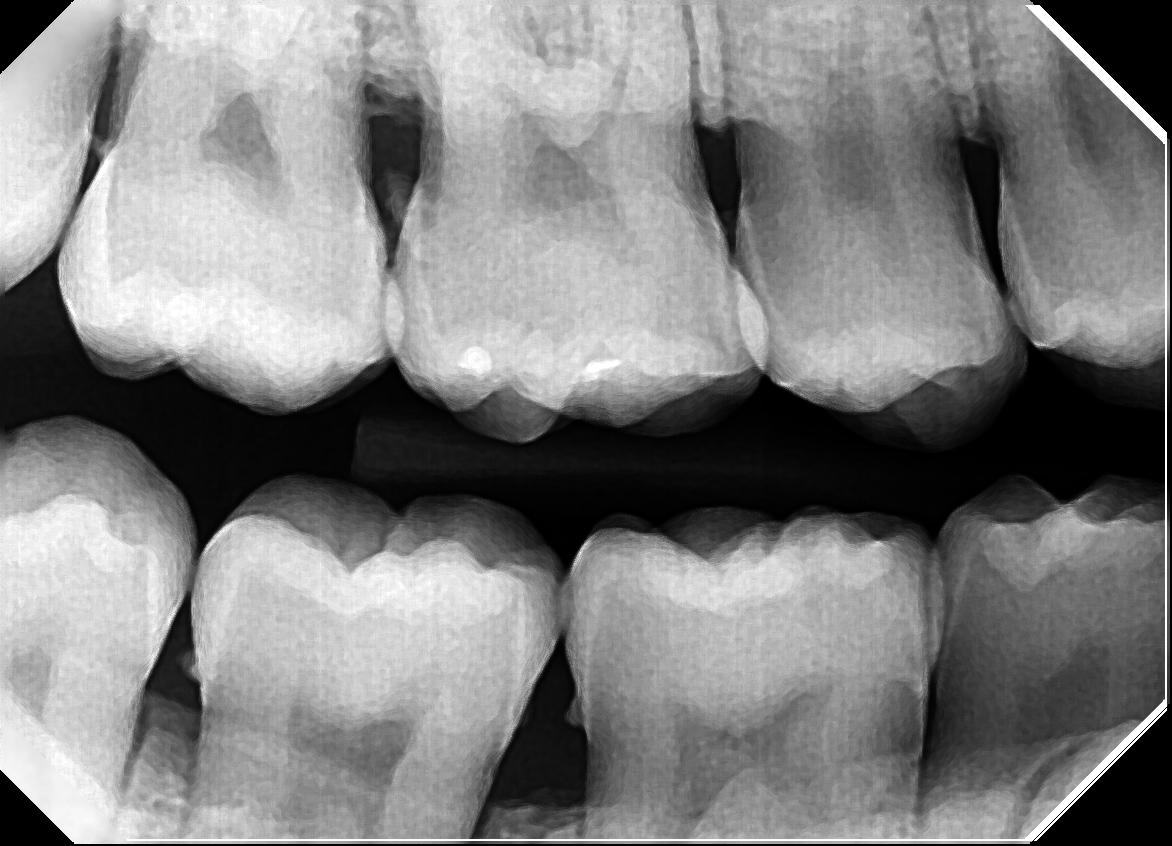

SRP Ideal Dentistry Dr. Maureen Palso, DDS

SRP Ideal Dentistry Dr. Maureen Palso, DDS Srp Dental Cost Scaling and root planing (srp), also known as deep cleaning, removes bacteria above and below the gum line when inflammation and bone loss are. Learn about the cost of each treatment below. Srp helps to reduce inflammation and increased tooth support. What happens if you don’t get srp when your dentist recommends it? What is scaling and root planing? Scaling. Srp Dental Cost.